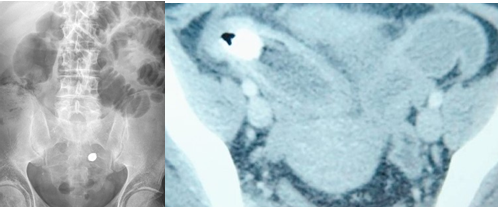

CT. Σημαντικό αιμάτωμα εκτεινόμενο στον προκυστικό χώρο (Ευγενική παραχώρηση Dr. V. Penopoulos).